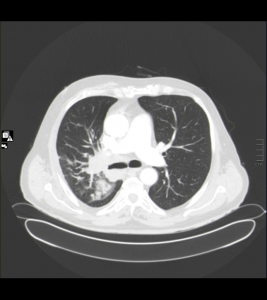

Ventana de pulmón